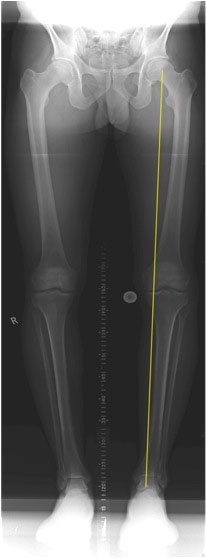

Every person's knee is aligned a certain way. Take a look at the long-leg X-ray below. If we draw a straight line from the centre of the hip to the centre of the ankle, if your leg is completely straight that line will go through the centre of your knee.

You will see on the X-ray in this normal person that the line does not actually go through the exact centre of the knee but instead it goes through the inner side of the knee. That is because most people are actually slightly varus - very very slightly bow-legged. If you say to a patient ‘You are varus. You are bow-legged”, they think they are not. They cannot understand it because when they look at themselves in a mirror they are sure they look straight. And that is right, they do look straight - the bowing is very subtle. Obviously there are extremes – you can be very bow-legged, completely straight, slightly knock-kneed or completely knock-kneed (knock-kneed is the reverse of bow-legged, and that is where the patient’s knees are coming slightly closer together and the weight-bearing line is going through the outer side of the knee).

So the key is getting you head around this idea of the weight-bearing line, which if your alignment is completely straight, will travel through the middle of the knee. But if you are slightly varus/ bow legged the weight-bearing line will pass through the inner or medial compartment of the knee, and the more bow-legged you are the more of that force will be going through the more medial position in your knee. And the reverse is true if you are knock-kneed. So if you are slightly knock-kneed that weight-bearing line will run slightly into the outer or lateral compartment of the knee, and if you are very knock-kneed it will be way over into the outer/lateral compartment of the knee. In fact if you drew the weight-bearing line it might even completely miss the lateral compartment, as is the case in that lady I showed you in the previous part of this course.